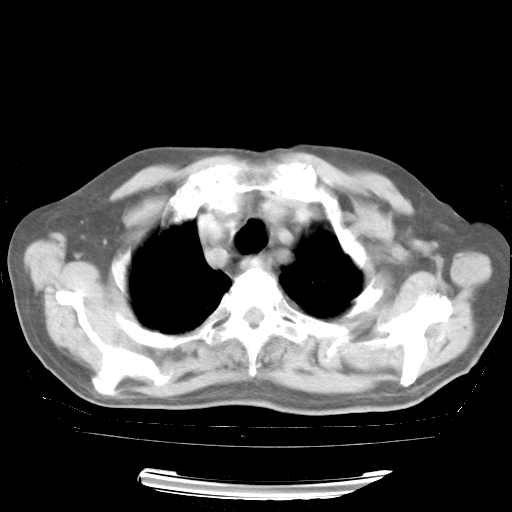

4月28日肺部CT——再次出现类似去年5月9日——透光度降低,“间质性”改变。